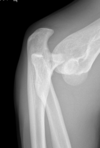

23

Monteggia and Galazzi

24

complications and clinical features of monteggia

A

1. radial nerve injury - wrist drop and parasthesia

2. compartment syndrome - refractory pain, distal parasthesia

3. compound - open and bone on view

How well did you know this?